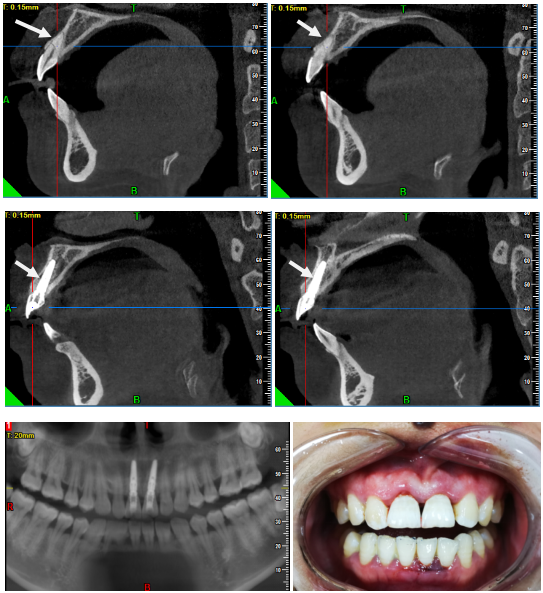

经过口腔CBCT检查确定,患者的两个中切牙牙根都斜行折断在根1/2左右,均无法保留,为了不影响患者的社交和生活,我们建议她进行即刻种植,这样可以避免择期种植前牙骨吸收而影响美观。

经过一系列检查和沟通,患者同意治疗方案,手术在当日下午三点半左右开始进行。由口腔科副主任钱晓晴主持即刻种植手术、我作为助手共同完成。钱主任以高超娴熟的技术,耐心细致的服务,令患者感觉很温馨,从而也忘记了手术的恐惧。为了让修复的效果更加逼真,我们决定利用患者拔下来的牙齿进行即刻修复。经过两个多小时加班加点的工作,患者看到最后镜子里的自己终于破涕为笑,说“你们太厉害了,这和我原来的牙齿一模一样,一点也看不出是假的”。作为医生听到患者这样的评价,我认为再多的辛苦付出都是值得的。也许这就是一位医者的最高荣耀吧!